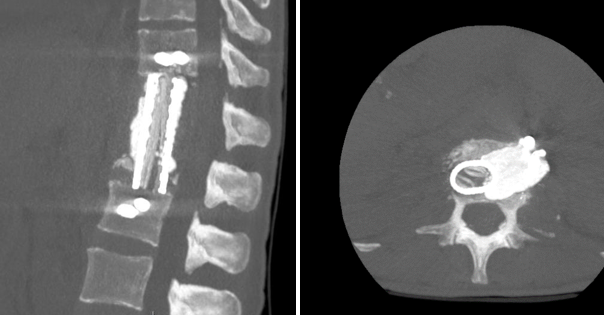

Для реконструкции передней опорной колонны использована титановая сетка, заполненная аутокостным материалом, в сочетании с цементным спейсером, содержащим гентамицин. В тела позвонков Т11-L2 бикортикально установлены спонгиозные винты (рис. 2), фиксированы на стержнях. Завершающим этапом установлены активные дренажи в резекционную полость и плевральную полость.

Рис. 2. Компьютерная томография (сагиттальная и аксиальная проекции). Замещение тел Tp2–L1 титановой сеткой с гентамициновым PMMA-спейсером

Составлено авторами по результатам данного исследования.